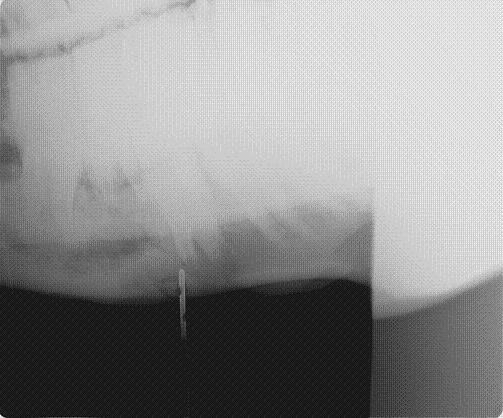

Posted on Monday, Mar 26, 2007 - 4:36 pm: Dear HA colleagues and Dr. O,Well, last Friday, my three "ex-PMU" mares arrived from Canada... not in perfect shape, of course, but, not dying either. However, 24 hours after their arrival, I noticed some swelling on the lower aspect of one mare's jaw, specifically, the straight portion of her left mandible about half way between her lower lip and masseter muscle areas. There also appeared to be two purulent tracts that were draining. Fortunately, this is one of the mares that has a sweet disposition and had allowed me to catch and lead her. Well, I thought this was not the usual place for strangles, and though it was Saturday night, I called my vet and he came out. He agreed that it was not likely strangles, but we cultured it anyway. In order to clean/irrigate the area, we had to sedate her and once she was "calm", he irrigated about 50-75 ccs of pus from the wound. He took some skull xrays of the area and suggested I start some antibiotics; though, I'm comfortable giving injections, we decided to start with oral Bactrim DS BID until the culture/sensitivities come back. Well, today he called to say that the xrays show a definitive mandibular abscess which does NOT appear to be dental in origin. We assume that she sustained a penetrating injury in the last few/several weeks that has produced this ???osteomyelitis of her mandible. Now, here's the big question: MEDICAL VS. SURGICAL TREATMENT???? And, does her pregnancy and/or her gestational age (still a big, big guess, of course, but for the past three years, she has always foaled in early to mid May... last year she was loose in the pasture with the stallion from May 15th until late November, but I'm still betting that she was bred during her foal heat). What is really the best course of therapy for this mare and what risk does that, or the lack of any therapy, expose her unborn foal to???? Thanks in advance for any thoughts! Martha

Posted on Monday, Mar 26, 2007 - 7:53 pm: So sorry Martha, poor girl she looks very nice. Only experience I've had was a friends mare got kicked it the lower jaw and it splintered and became abcessed. The vet just had us keep it clean and medicated. I pulled out 2 small bone splinters and thought more should have been done but not my mare. She did finally get well??!! Dr. O will have good ideas. All the best Cindy |

Posted on Tuesday, Mar 27, 2007 - 9:22 am: Thanks for everyones' concerns and comments... Well, right now we are getting ready to load in the trailer and take a ride to our local (large) equine practice that has just recruited an equine surgeon from VA Tech. Basically, my beloved ambulatory vet told me he didn't think he could do more (surgically) in the field and I assume that was based his interpretation of the xrays (so, Dr. O, I don't yet know the answer to your question); the xrays were, of course, take with a portable, hand-held machine, so perhaps they are less than ideal. Basically, when we get to the clinic today, we'll get an exam, some additional xrays I suspect, and then some sedation to explore and I/D the wound further; when I spoke with the clinic last night they also mentioned the need to determine whether there is any communication of the wound with the oropharynx (I may have forgotten to mention that on Saturday when my local vet was irrigating the wound, the mare started "chewing" as if something was getting in her mouth...) So, more to come...Martha |

Posted on Wednesday, Mar 28, 2007 - 5:08 pm: O.k... Most physicians have been taught the expression "when you hear hoofbeats, think horses, not zebras" and that appears to be true in veterinary medicine also! Here's the update... (BTW, Dr. O, my vet did take obliques in the field on Saturday evening) My mare has an "osteolytic lesion of the left hemimandible" which, based on the contrast fistulagram performed, originates from her 3rd premolar. At the large equine clinic we visited yesterday she was sedated again, with detomidine, then butorphanol, got the additional xrays and contrast fistulagram, then got an incredible exam of the oropharynx with the hopes of extracting the 3rd premolar. Sadly, we discovered that the tooth was fractured down to almost the gumline and the surgeon was unable to extract it in the normal fashion. He feels that a general anesthetic is the only reasonable approach now in order for the tooth remnant to be removed via an intraoral route, or even possibly through a mandibular incision. He also thinks that it is likely she's had this for "years" and that we can wait for any further therapy. He thought that the possibility of hypoxia during a GA would put the foal at unnecessary risk, given the chronicity of this problem with the mare. So, she should foal in the next month or so, then after 60 to 90 days we'll go in for the definitive surgery later in the summer. Meanwhile, she's still on antibiotics and I should hear about the culture later today, though I know it's likely to be "mouth flora". I'll keep everyone posted... Thanks!Martha |

| Member: paul303 |

Posted on Monday, Apr 2, 2007 - 1:25 am: Boy, that is nasty. It almost looks like there is a possibility of involvement of the adjacent teeth. No wonder this mare is reluctant to have you work around her mouth. If the fistulas remain open and draining until she foals, she should be OK. Best of luck! |